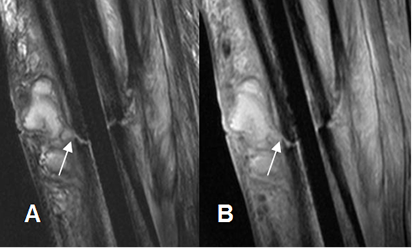

Fig 45 C. Osteomielitis crónica.

A: RM sagital en T2 y B: RM sagital en STIR. Igual paciente anterior. Se encuentra trayecto fistuloso que se origina en el foco de fractura y comunica con una colección, por osteomielitis crónica.